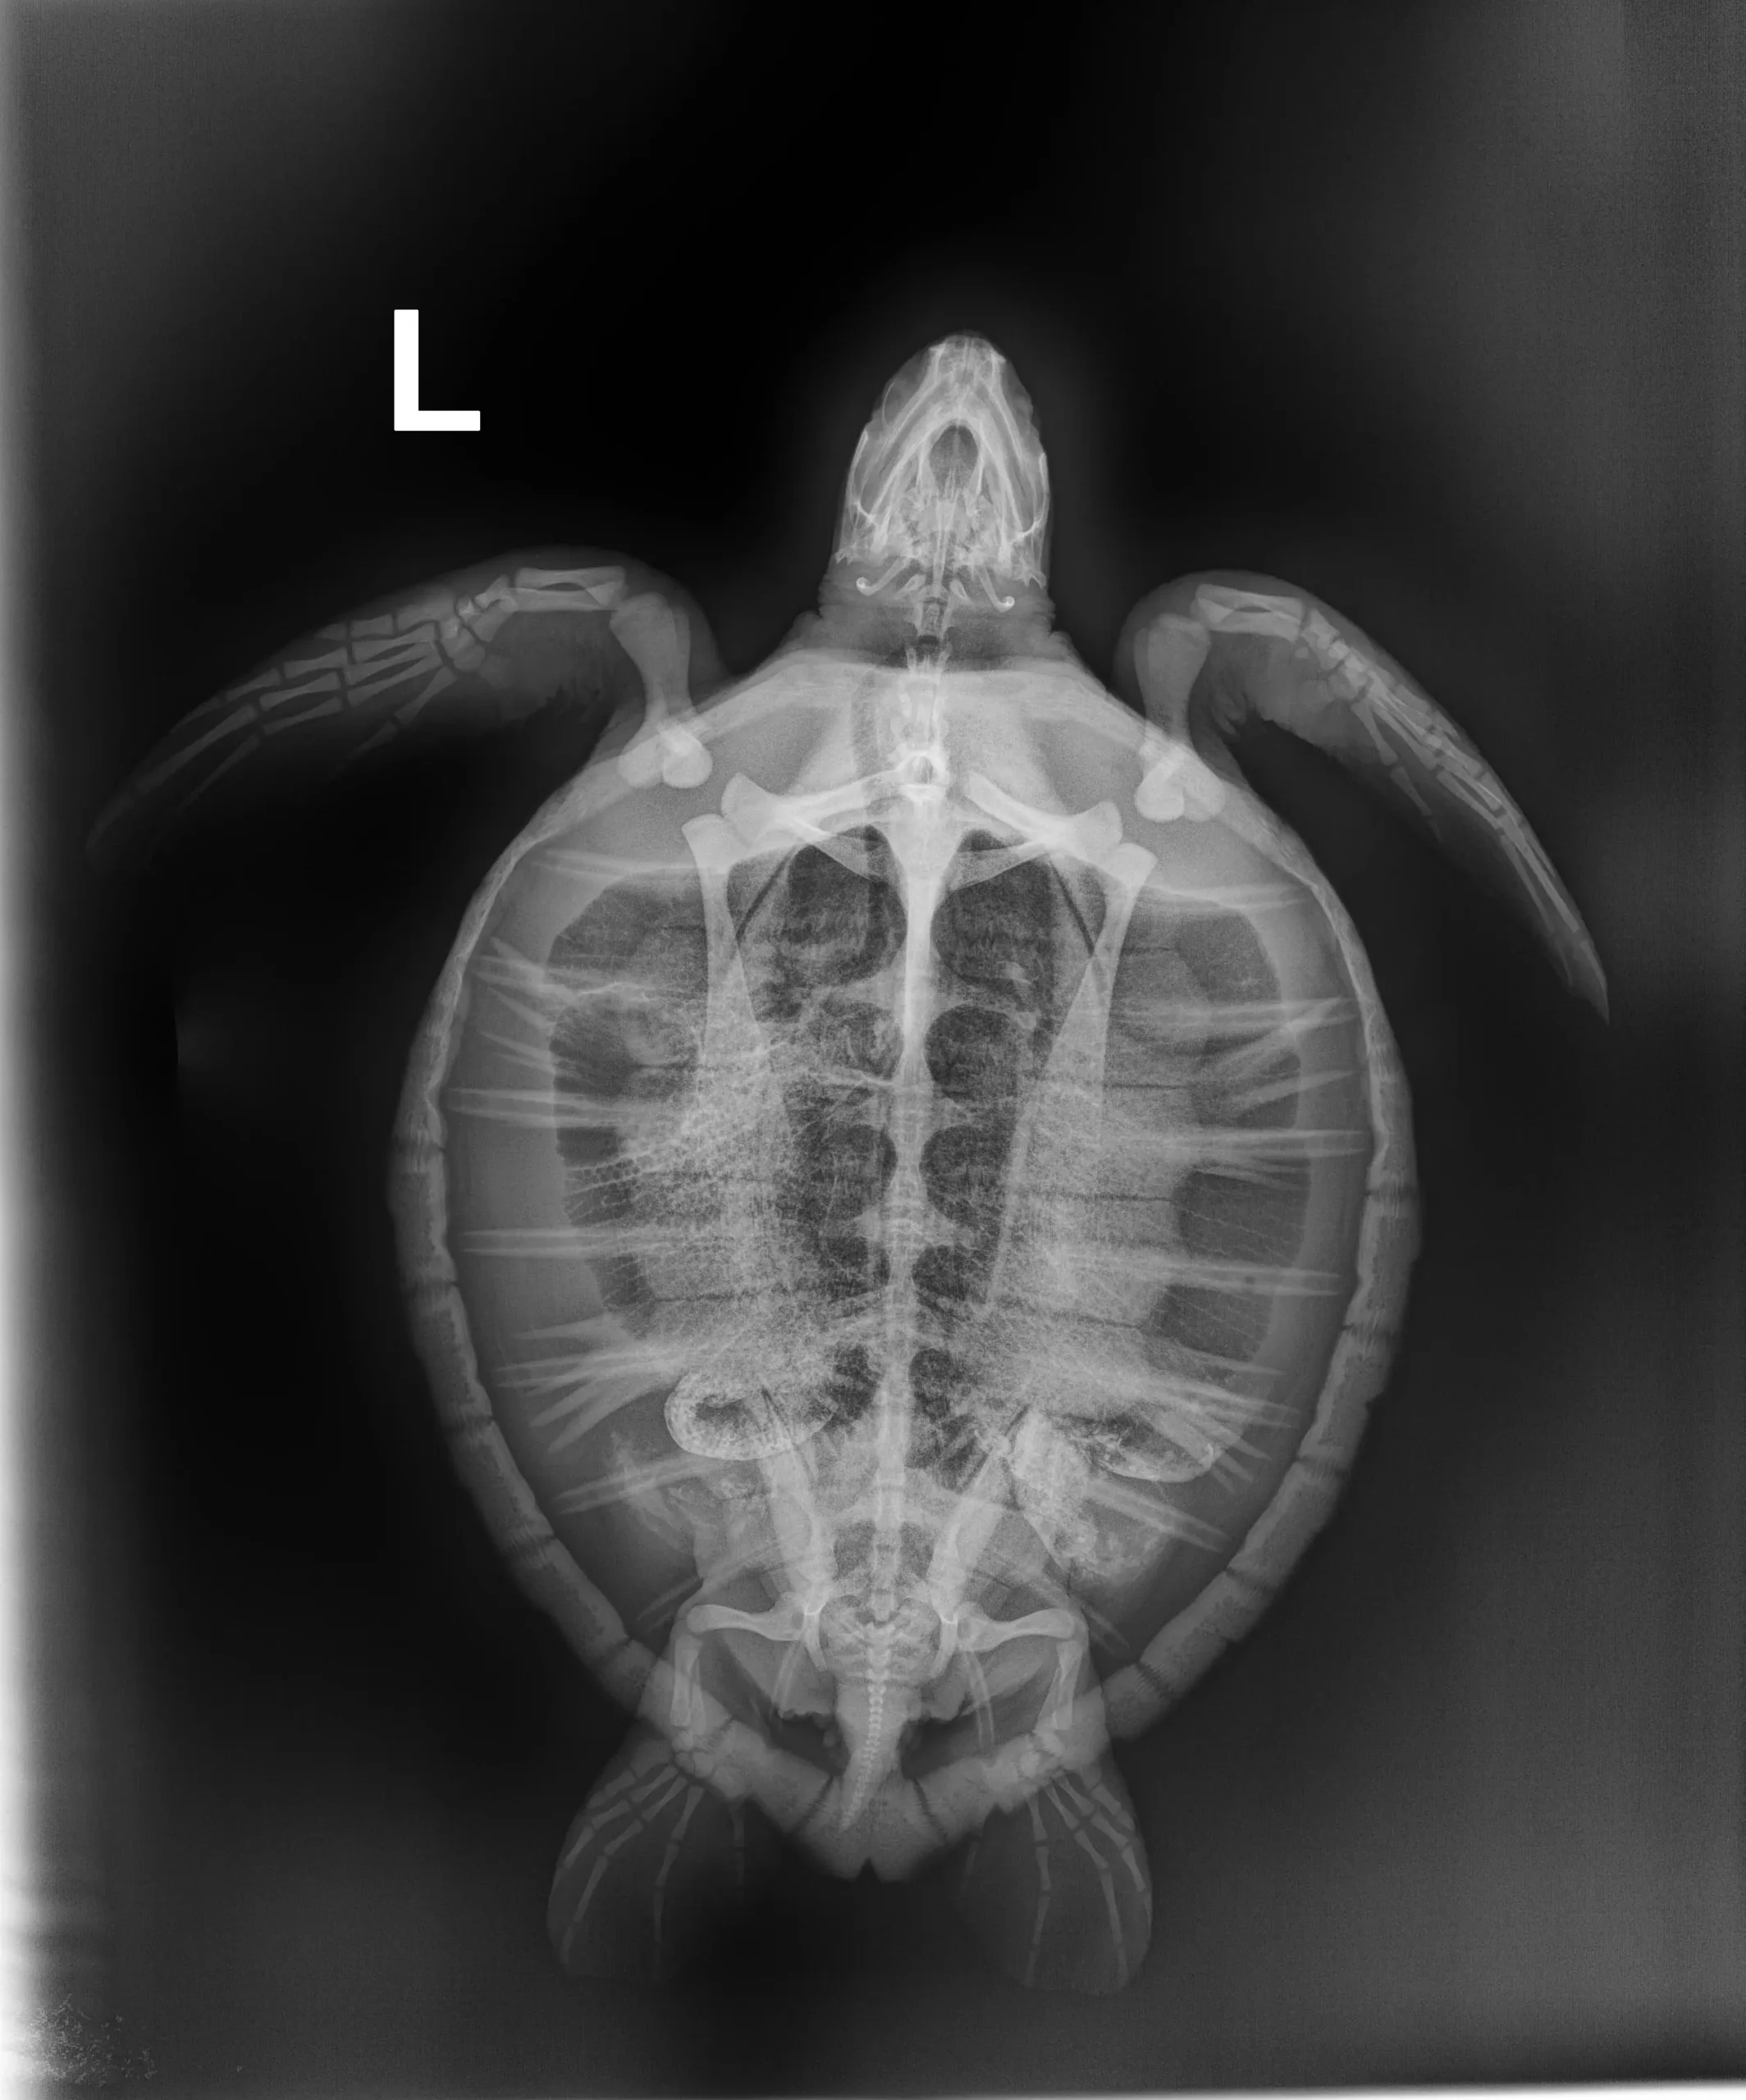

3.9 lbs non-FP juvenile green

Minor abrasion on plastron and all 4 flippers, moderate abrasions on carapace, had brown mucus like substance coming from mouth